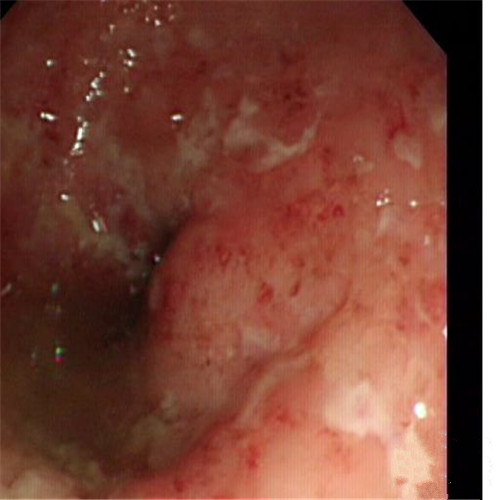

潰瘍性結腸炎治療前後對比

輕微潰瘍性結腸炎前後對比